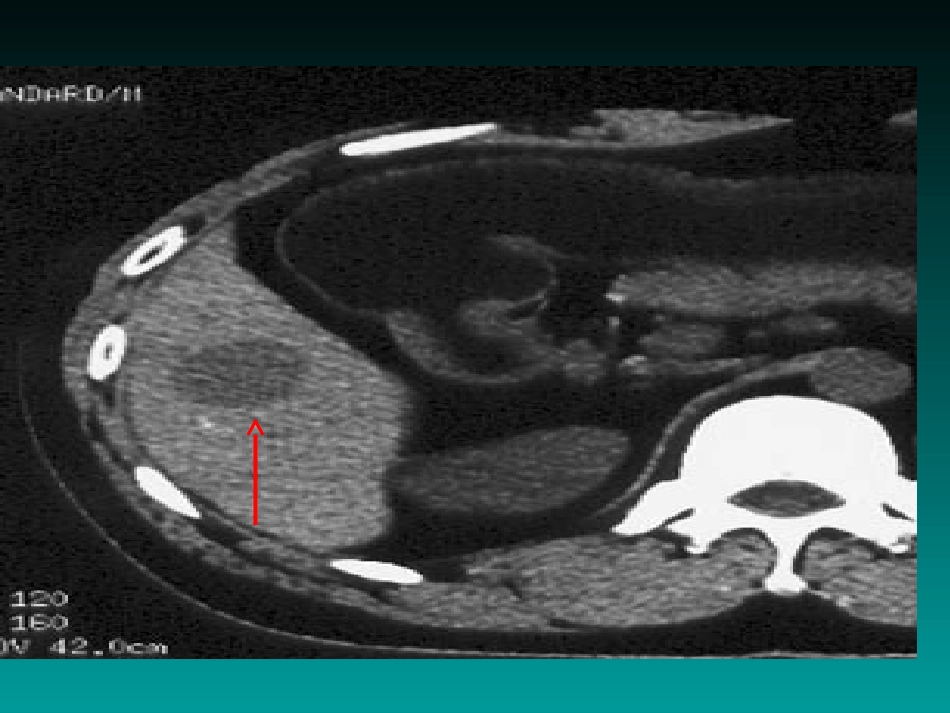

肝血管瘤•肝血管瘤是肝脏的良性肿•瘤,占肝良性肿瘤的84%。•人群发病率5%~7%。临床表现clinicalmanifestation一般无症状(85%),多于体检时偶然发现;•当瘤体直径>5cm(巨大海绵状血管瘤)时,可出现上腹部胀痛、食欲减退;瘤体破裂可引起瘤内、肝包膜下或腹腔内出血,严重者出现休克。肝血管瘤的症状•临床症状上可将肝海绵状血管瘤归纳于4种类型:•(1)无症状型:肿瘤≤4cm,B超、CT等影像学检查或剖腹探查时发现。•(2)腹块型:肿瘤增长至一定大小,虽未产生自觉症状,但病人无意中发现腹部肿块。•(3)肿块压迫型:约占50%~60%•(4)内出血型:瘤体发生破裂,腹腔内出血、心悸、出汗、头昏、四肢湿冷、低血压、休克等肝血管瘤分类•(1)(1)海绵状血管瘤海绵状血管瘤((最常见)最常见)•(2)(2)硬化性血管瘤硬化性血管瘤•(3)(3)血管内皮细胞瘤血管内皮细胞瘤•(4)(4)肝毛细血管瘤肝毛细血管瘤概述outline•常见、良性•发病率1%-10%•好发于女性•多见于30-60岁•90%为单发••肝海绵状血管瘤•肝血管瘤的病因•多认为与先天发育异常有关,可能由下列因素引起。••1.毛细血管组织感染后扩张变形;••2.肝组织局部坏死后的肝组织周围血管充血、扩张、最后形成空泡状;•3.肝内区域性血循环停滞后,致血管形成海绵状扩张。肝内持续性静脉血瘀,导致静脉膨大;••4.肝内出血、血肿机化、血管再通后形成血管扩张;••5.血管发育异常致血管海绵状扩张。肝动脉末梢先天性畸形。•6.可能与雌激素有关。病理表现pathologicalappearance•大体肿瘤组织切面•纤维化•血栓•囊性变性•钙化(偶尔)病理表现pathologicalappearance血窦和纤维组织间隔,形成海绵状结构血窦腔内衬单层扁平内皮细胞,窦腔内充满血液•光镜下肝血管瘤的并发症肝血管瘤的并发症•1.肝血管瘤破裂:可引起急腹症或内出血症状;•2.血小板减少症和低纤维蛋白原血症:少数病人常因凝血机制障碍而引起此症;•3.肝脏肿大:血管瘤长大时会引起肝脏肿大;•4.肝囊肿:约10%的病人可并发肝囊肿;肝血管瘤诊断依据•1.肝区胀痛,肝大或触及包块。2.彩色B超示肝血管瘤样改变。3.CT检查:肝内有密度均匀的低密度区,增强后肿瘤边缘区可出现“C”形增强带。•4.MRI检查:•5.肿瘤标志物检查:AFP,CEA,影像学表现imagingfindings(CT)•清楚的圆形或类圆形•低密度影•CT平扫诊断及鉴别诊断diagnosisanddifferentialdiagnosis诊断要点:平扫---CT:圆形或类圆形低密度影MR:圆形或类圆形长T1长T2异常信号增强扫描:典型特点---早出晚归,快进慢出诊断及鉴别诊断diagnosisanddifferentialdiagnosis鉴别诊断肝囊肿肝脏转移瘤原发性肝癌小结对于诊断肝海绵状血管瘤:1、动态增强扫描是关键;2、早出晚归(快进慢出)肝脏海绵状血管瘤的鉴别:1、肝囊肿-无强化;2、原发性肝癌-快进快出;3、肝转移瘤-环形强化,牛眼征。肝血管瘤治疗选择肝血管瘤治疗选择•一、手术治疗:肝血管瘤剥离术、肝叶、肝段切除术开腹手术,手术创伤大,术后恢复慢二、肝动脉结扎手术三、肝动脉介入栓塞治疗四、肝移植五、皮质类固醇类药物六、腹腔镜七、射频消融术特色治疗一:高频彩超微创介导治疗术精准穿刺:在超声引导下经皮经肝穿刺针准确进入病灶,注入药物。肝血管瘤高频彩超微创介导治疗•【操作技术】•一般采用21~23G(相当于6~8号针)带针芯细针。••(1)病人取仰卧位或侧卧位,先用探头检查肝脏病变,选择穿刺目标,初步确定穿刺部位及穿刺径路。••(2)常规消毒穿刺部位,铺消毒巾,用探头显示穿刺病灶,再次确定适宜的穿刺点和方向及深度。••(4)固定穿刺探头,当病灶显示清晰时,将穿刺针进针,待进入皮下,即令病人屏气或浅呼吸,继续穿刺进针。在监视屏上,严密监视穿刺针的针尖回声的前进方向,直至进入肝脏血管瘤内抽有回血即表明已到达病变区。若在进针过程中针尖显示不清,可适当调整探头角度,一般即能显示针尖位置。••(5)进入病灶内拔出针芯抽有回血,嘱病人浅呼吸或平静呼吸,接装有药液注射器,缓慢注药,药物注射完毕后,迅速拔出穿刺针。1周后做第二次治疗,根据瘤体大小...